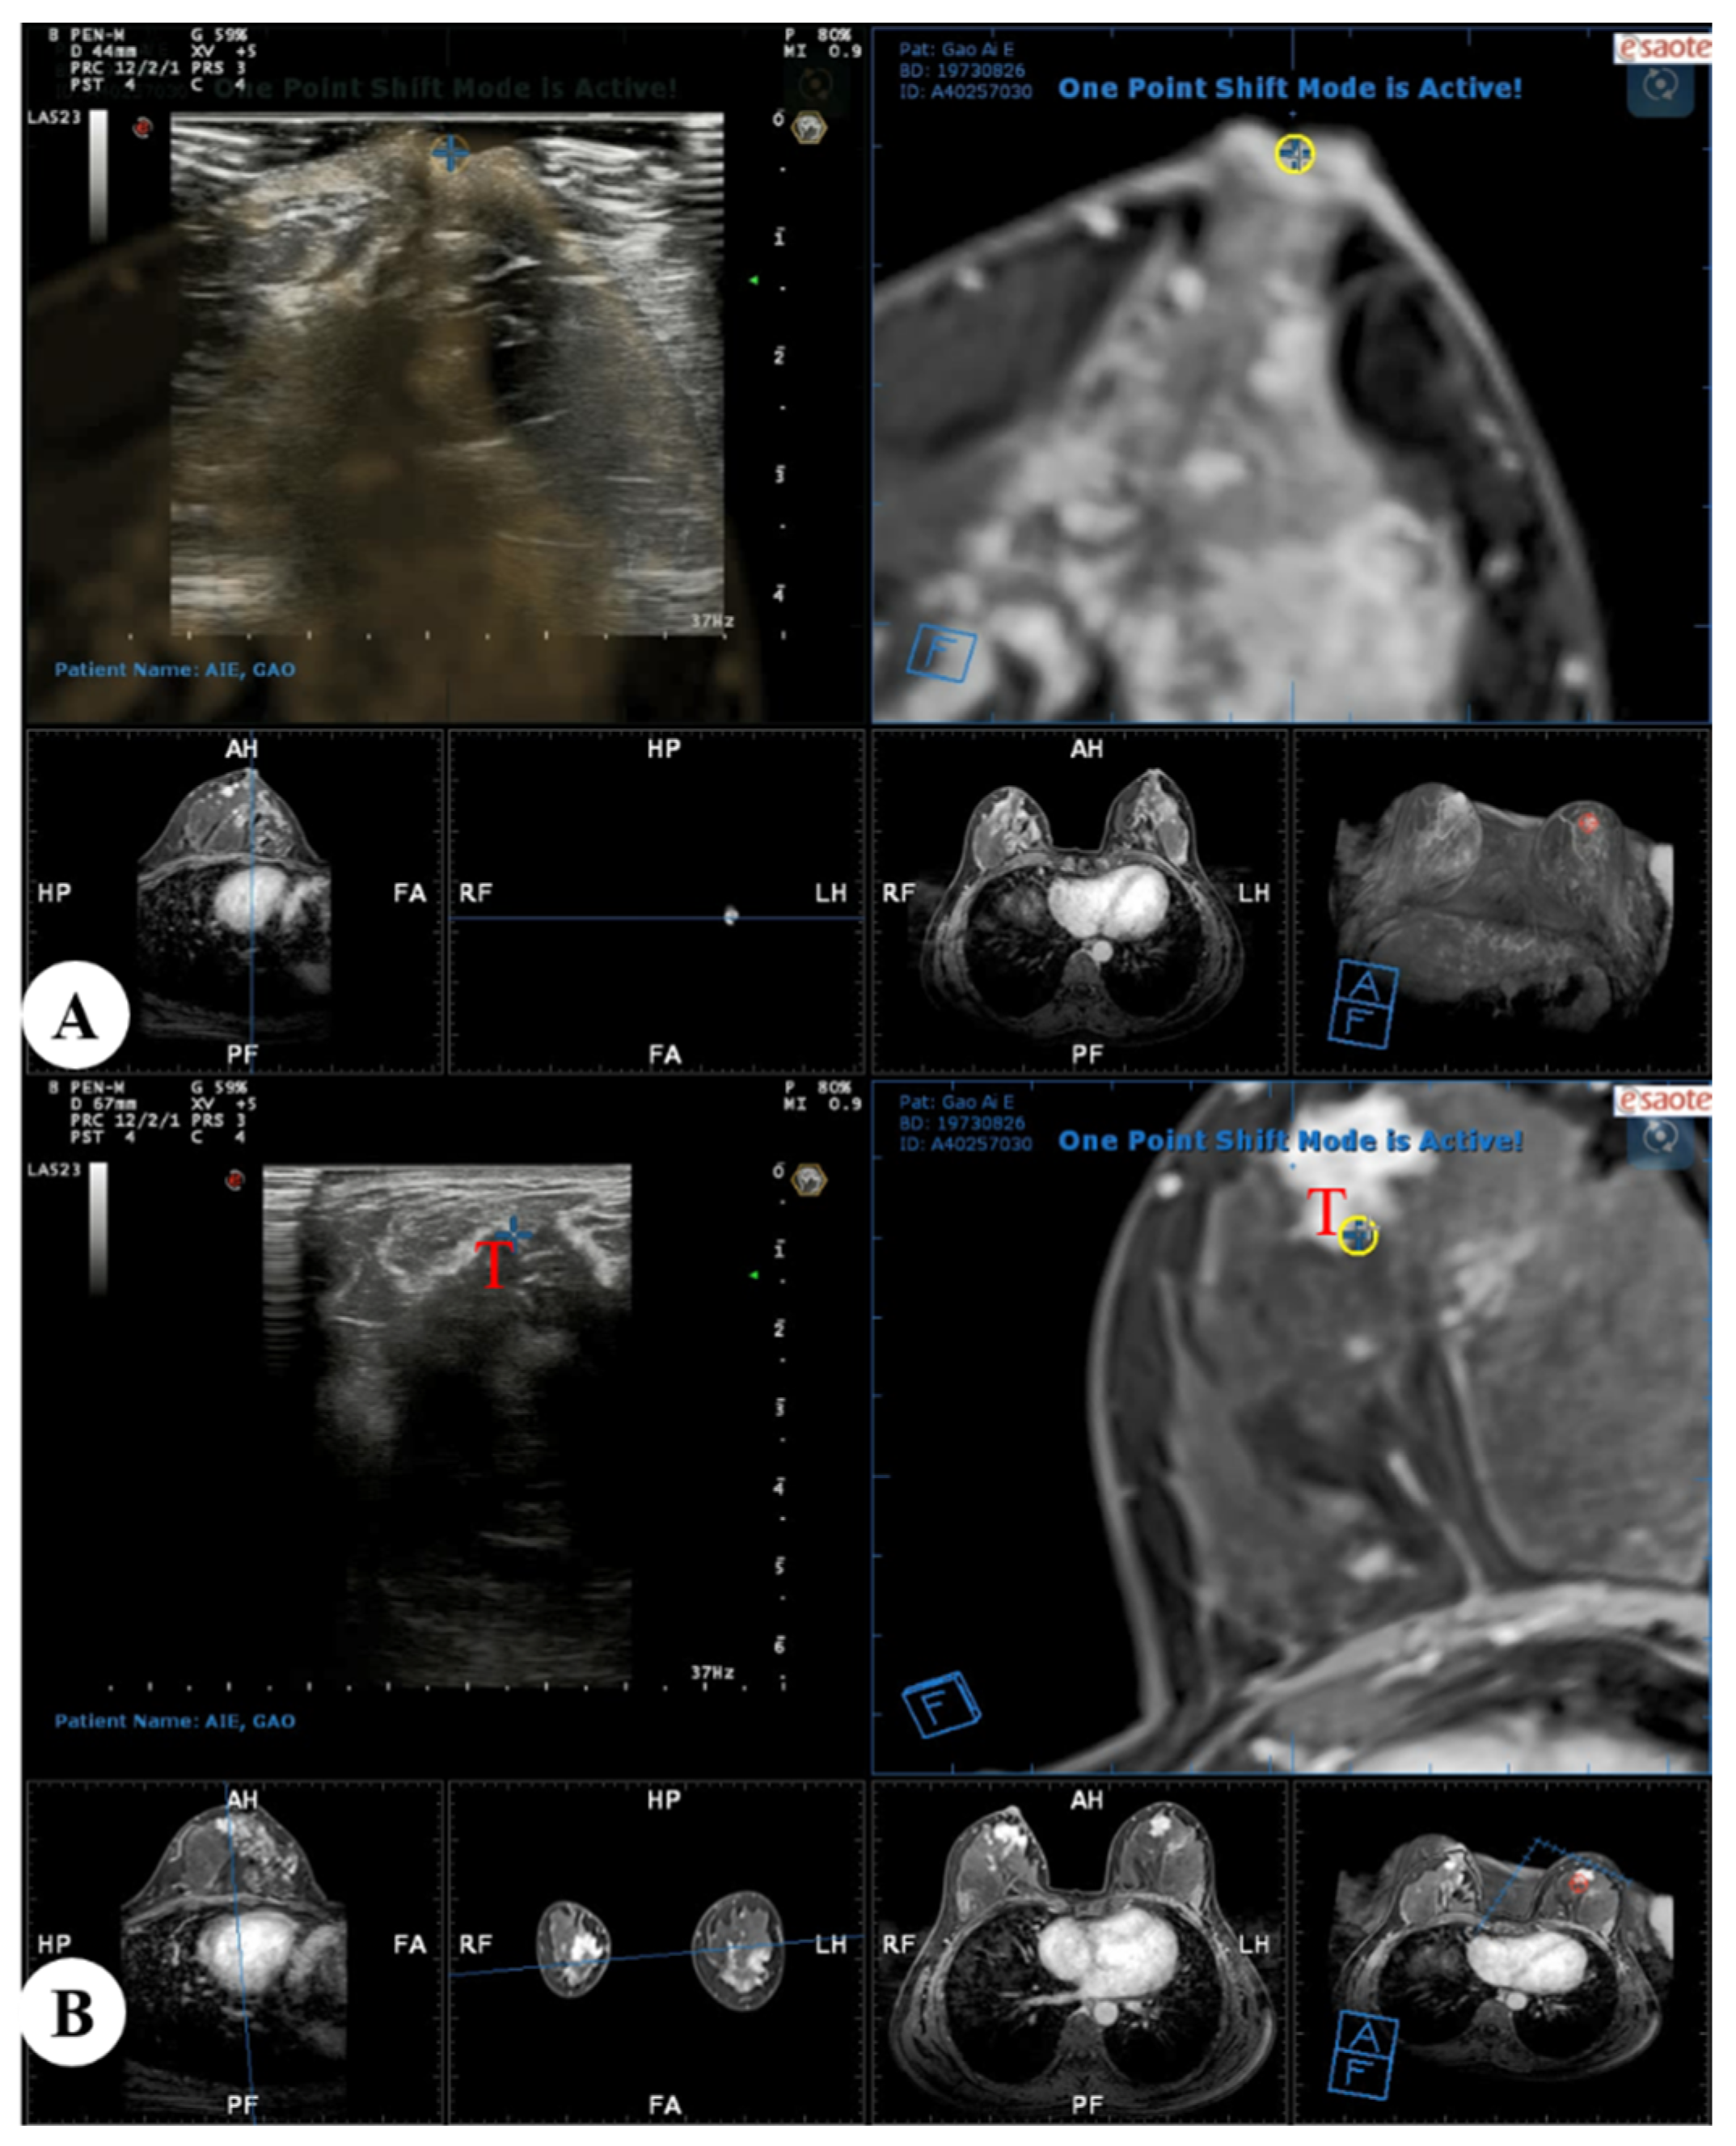

In the present study, real-time US with virtual navigation processes were performed in the prone position using a special prone positioning frame (Figure 2). The patient lay prone to the device, allowing both breasts to droop naturally in the hole above, and the operator performed the US examination below the hole. After axial alignment was performed at the nipple level, and the contour of the breast was aligned, the surrounding tissues such as mammary fascia, blood vessels, or fat lobules were then matched. The Virtual Navigator system calculated spatial information and displayed an MRI-MPR image corresponding to the US image in real time. Subsequently, the operator moved the transducer gradually to narrow the scan range on US images and search the location of the suspected corresponding lesion (Figure 3). When a suspicious lesion was identified with real-time US with MRI virtual navigation, we analyzed its sonographic features and evaluated the lesion’s location and surrounding tissues and marked it. Then, the patient was put in the supine position, and a US-guided core needle biopsy or needle localization was performed referring to the area identified on the prone US.

Figure 3.

Real-time US with virtual navigation was performed in the prone position: (A) A co-registration process between real-time US and MRI-MPR images was performed with the nipple as a reference point, and the contour of the breast and internal anatomic landmarks were aligned; (B) Search and localization using real-time US with virtual navigation of the corresponding suspected enhanced lesion (T, target) identified on MRI alone. US = ultrasound; MRI = magnetic resonance imaging; MPR = multiplanar reconstruction.